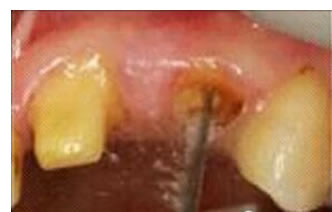

圖3:根管內(nèi)殘留物

圖4:超聲去除根管殘留物。

根管壁殘留物的存在直接影響著纖維樁的粘接和固位,是纖維樁脫落的主要原因之一。由于圓形的根管鉆和根管形態(tài)不完全一致,終鉆預備完成后大多情況下樁道側(cè)壁會有不同程度的牙膠和封閉劑等殘留物附著(圖 3)。因此,建議X線檢查根管預備情況,選用超聲潔牙機更換較細工作尖進入根管,徹底去除樁道根管壁上附著的殘留物(圖4)。使用根管銼去除殘留物時,很難清除干凈;禁止使用牙膠溶劑如丁克除、氯仿等有機溶劑去除殘留物,以免破壞根尖區(qū)牙膠的封閉,或有機溶劑粘附于根管壁形成蠟膜而影響粘接。